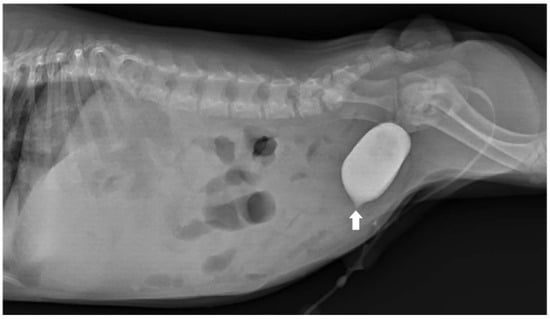

To assess for a persistent urachus, a positive contrast cystogram (KXO-80s, Toshiba, Tokyo, Japan) was performed using iohexal contrast medium (10 mL/kg, diluted to 100 mg I/mL; Omnipaque, GE HealthCare, Bangkok, Thailand). The cystogram demonstrated a contrast-filled structure extending from the apex of the urinary bladder as a convex outpouching of the lumen without evidence of contrast leakage toward the umbilicus (Figure 2). These findings were considered consistent with vesicourachal diverticula. An abdominal ultrasound examination was performed by using a real-time scanner (LOGIQ E9, GE, Fairfield, CT, USA) with a 13 MHz broadband linear transducer. Abdominal ultrasonography revealed a markedly dilated common bile duct (CBD; diameter 0.45 cm) and found an abnormal fistulous tract extending toward the umbilical region, while the gallbladder was not visualized (Figure 3). These findings raised the suspicion of an anomalous extrahepatic biliary tract or an ectopic remnant ductal structure. Therefore, an abdominal computed tomography (CT) scan (Optima 660, GE HealthCare, Bangkok, Thailand) with fistulogram was performed under general anesthesia (induction: propofol [8 mg/kg IV, Troypofol, Troikaa Pharmaceuticals Ltd., Gujarat, India], maintenance: 3% sevoflurane inhalation [Sevo, Singapore Pharmawealth Lifesciences Inc., Laguna, Philippines]). Iohexal contrast medium (2 mL/kg, 300 mg I/mL) was injected via a feeding tube inserted through the umbilicus. The fistulogram demonstrated a tubular tract filled with contrast medium extending from the umbilicus to the CBD and biliary tree, with passage of contrast into the duodenum (Figure 4). The CBD was dilated with contrast medium. In addition, CT imaging revealed the absence of the gallbladder, consistent with agenesis. Together, these findings were compatible with a congenital umbilicobiliary fistula with gall bladder agenesis. All the imaging techniques were performed and interpreted by a veterinary radiologist certified by the Thai Board of Veterinary Surgeons (sub-specialty of veterinary diagnostic imaging).

Figure 2. Lateral radiographic view of the abdomen of the dog. Positive contrast cystogram demonstrated a small contrast-filled outpouching at the urinary bladder apex (arrow) without connection to the umbilicus. The dog was diagnosed as having vesicourachal diverticula.